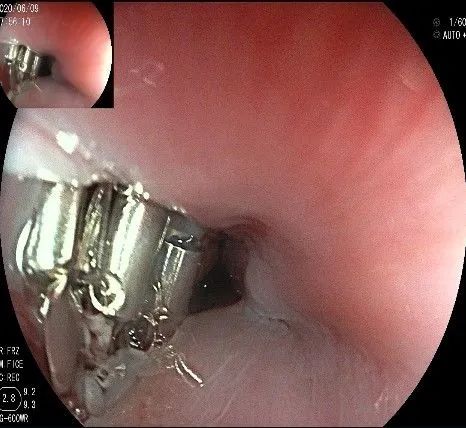

夹闭创面的时候做胃镜吸引,利于创面闭合。

创面夹闭完成,反复冲洗观察,无出血及穿孔。结束手术,等待病理结果。